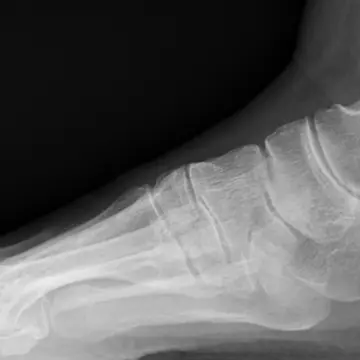

アキレス腱が柔軟だと、足底のアーチがくずれない。

アキレス腱が硬いと、足底を押しつぶし、偏平足に。

「正しい歩き方の流れを説明しますと、まずかかとから着地して、次に足裏全体が接地します。そこから重心が前方に移動する過程で、すねが前に倒れます。アキレス腱が柔軟でしっかり前に倒れる人は、足底のアーチが沈み込み衝撃を吸収。さらに重心が前方に移動するにつれてアーチが回復し硬い状態になり、足指で地面をしっかりとけり出すことができます。このけり出しがしっかりできれば、次に足を前に出すときの地面と足のあいだにクリアランスが確保されるので、そうつまづくことはありません」(久道先生)

「アキレス腱が硬くてすねがスムーズに前に倒せないと、かかとから足裏への体重移動が急激におこなわれるため、足底のアーチの沈み込みと回復に十分な時間的な余裕がなく、足指で地面をしっかりとけり出すことができません。いわゆるベタ足、すり足の状態になり、つまづきやすくなってしまうのです」(久道先生)